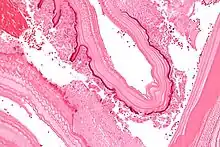

Larval/hydatid cyst stage

From the embryo released from an egg develops a hydatid cyst, which grows to about 5–10 cm within the first year and is able to survive within organs for years.[17] Cysts sometimes grow to be so large that by the end of several years or even decades, they can contain several liters of fluid. Once a cyst has reached a diameter of 1 cm, its wall differentiates into a thick outer, non-cellular membrane, which covers the thin germinal epithelium. From this epithelium, cells begin to grow within the cyst. These cells then become vacuolated, and are known as brood capsules, which are the parts of the parasite from which protoscolices bud. Often, daughter cysts also form within cysts.[16]

The cysts found in those with cystic echinococcosis are usually filled with a clear fluid called hydatid fluid, are spherical, and typically consist of one compartment and are usually only found in one area of the body. While the cysts found in those with alveolar and polycystic echinococcosis are similar to those found in those with cystic echinococcosis, the alveolar and polycystic echinococcosis cysts usually have multiple compartments and have infiltrative as opposed to expansive growth.[9][10]